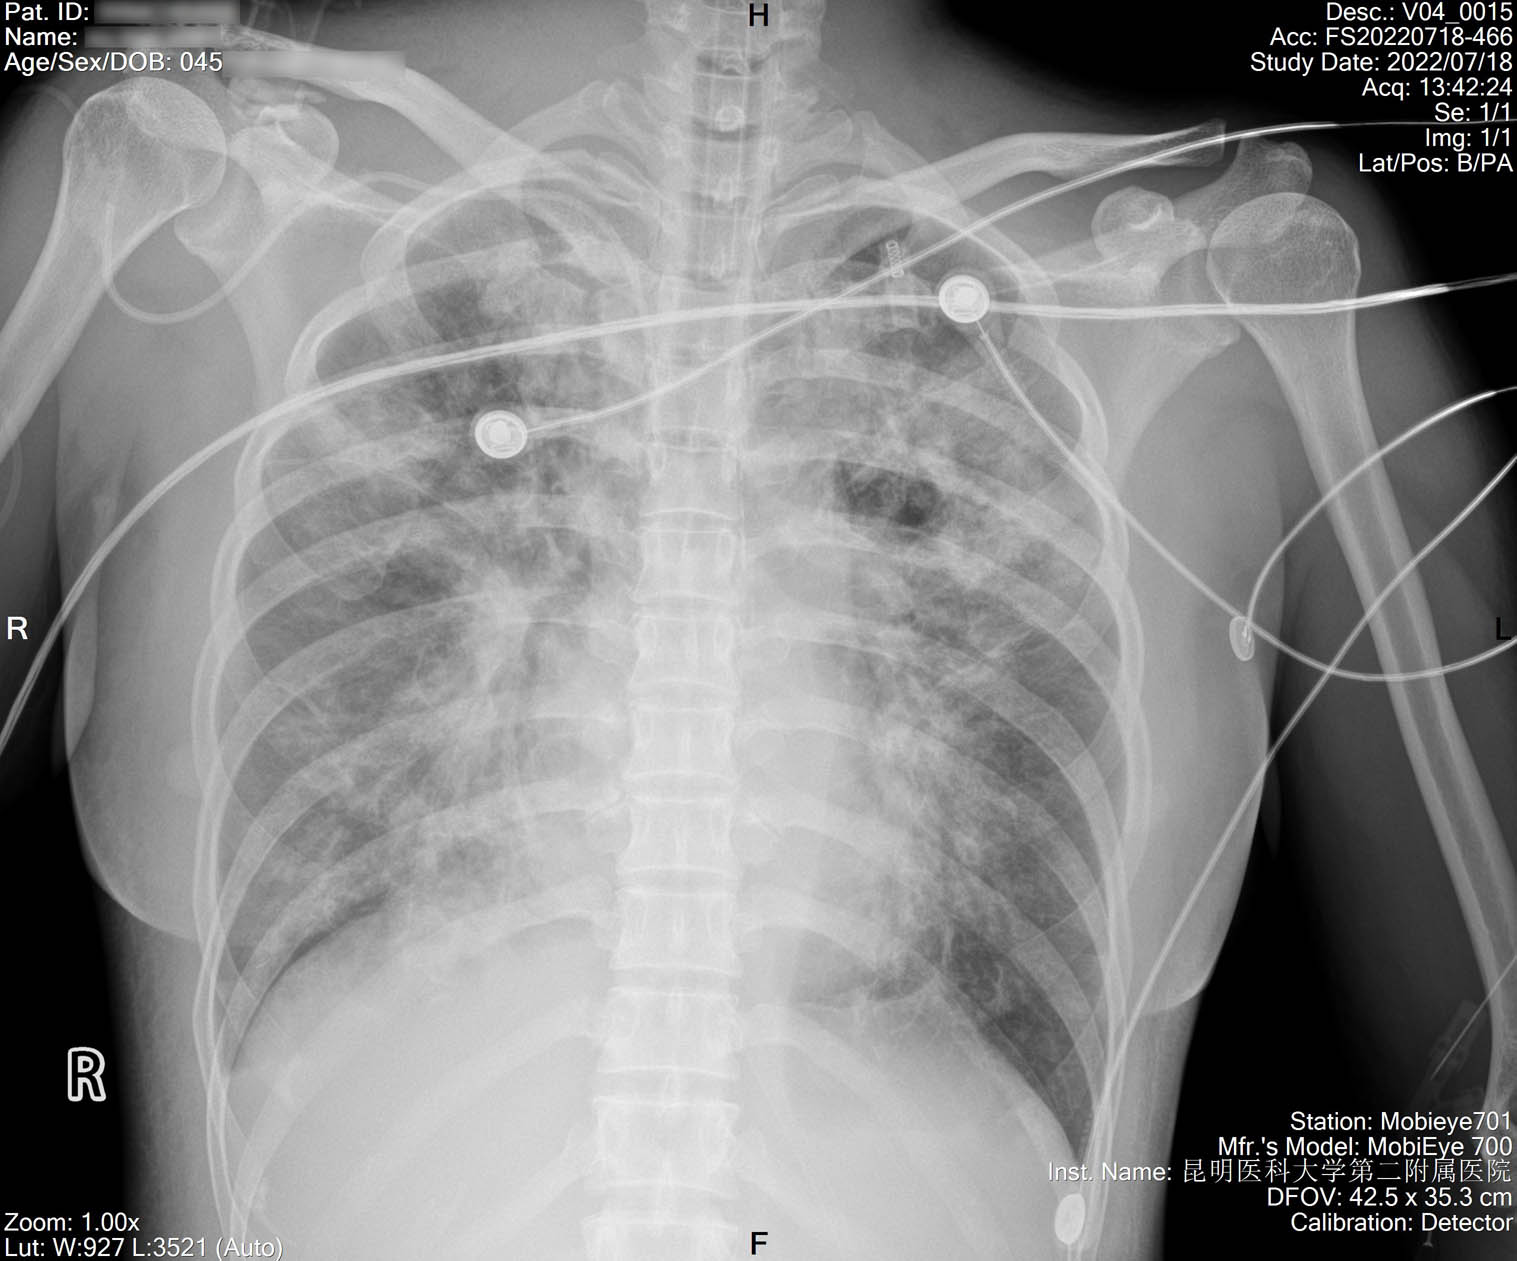

2022-07-18_胸片